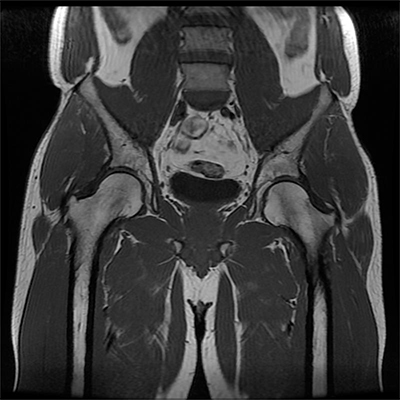

MRI Scan: This study uses a large magnetic field and radio waves to produce images that help in detecting damage to soft tissue. In some cases of snapping hip syndrome, an inflamed bursa can be identified on MRI.